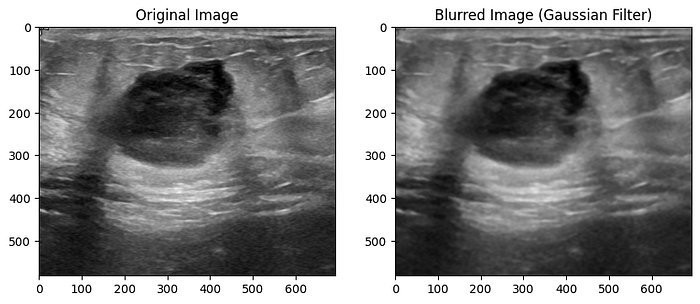

A Gaussian blur is a type of image blurring that involves convolving the image with a Gaussian distribution. This process smoothens the image by reducing high-frequency noise and fine details, which results in a 'blurred' like appearance. The extent of blurring is controlled by the standard deviation (sigma) of the Gaussian distribution. A larger sigma value leads to a stronger blur effect, and a smaller value results in milder blurring.

Much like other augmentation methods, in medical imaging, blur augmentation can simulate the effects of motion or imperfections in imaging devices. For instance, when capturing an MRI or CT scan, patient movement or slight vibrations can cause blurring in the resulting images.

To apply the Gaussian blur, you can use the gaussian_filter() function within the scipy library.